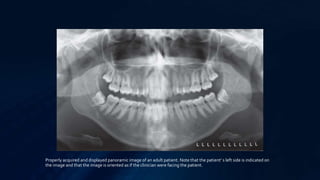

Properly acquired and displayed panoramic image of an adult patient. Note that the patient’ s left side is indicated on

the image and that the image is oriented as if the clinician were facing the patient.